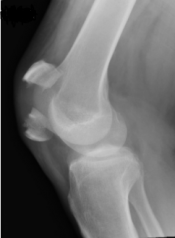

WhWhat’s the Diagnosis? Gepost op 12 november 2020 door netwerkvsseh What’s the Diagnosis? @emdaily.cooperhealth.org Dit delen: Delen op X (Opent in een nieuw venster) X Share op Facebook (Opent in een nieuw venster) Facebook Delen op LinkedIn (Opent in een nieuw venster) LinkedIn E-mail een link naar een vriend (Opent in een nieuw venster) E-mail Afdrukken (Opent in een nieuw venster) Print Vind-ik-leuk Aan het laden... Gerelateerd